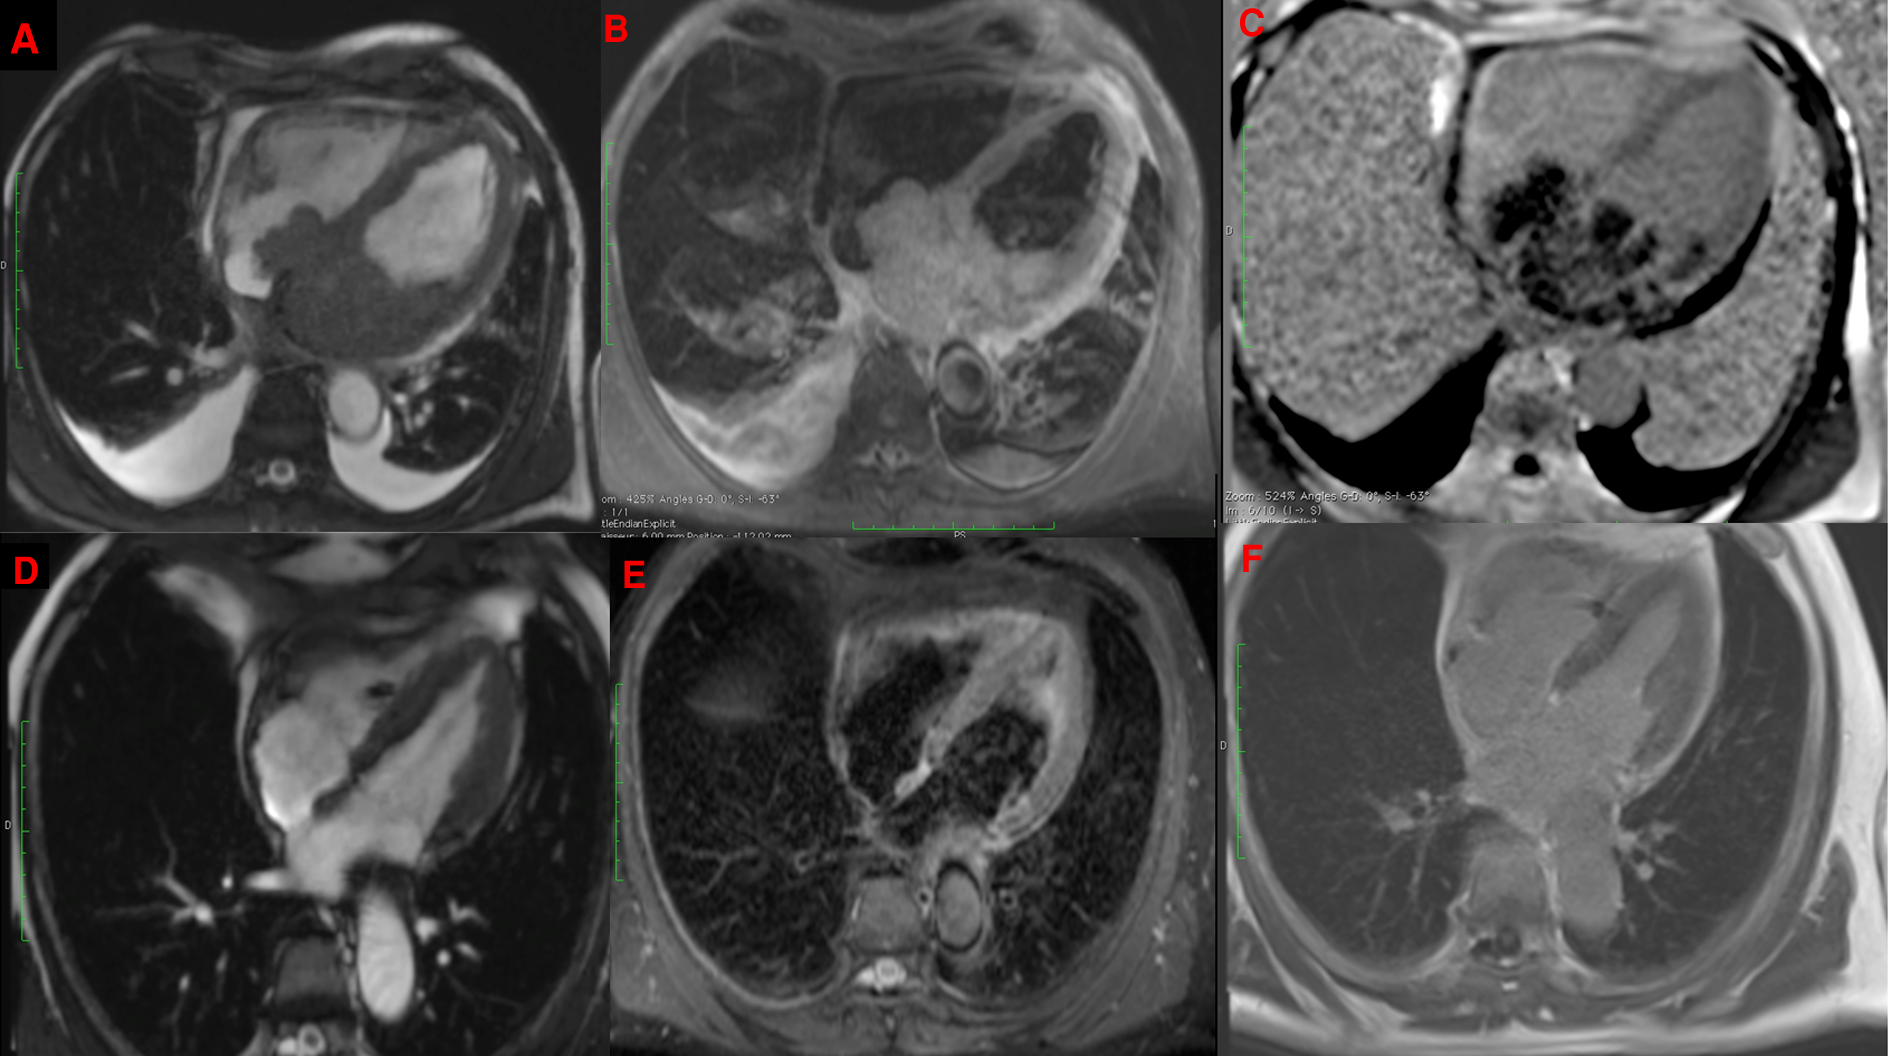

Figure 2

CMR showing a bulky mass extending throughout the left atrium, infiltrating the interatrial septum and right atrium, on cine imaging sequence (A), slightly hyperintense on fat-saturated T2-weighted imaging (B) with heterogeneous enhancement on late gadolinium enhancement sequences (C) with complete disappearance after 6 cycles of R-CHOP in the same sequences (D–F).

In March 2022, a 63-year-old man without notable past medical history presented with rapidly progressive exertional dyspnea associated with night sweats. The electrocardiogram revealed complete atrioventricular block (AVB) with a heart rate of 40 beats per minutes and narrow QRS complexes. Lab tests showed anemia with hemoglobin at 9 g/dl, normal renal function and a biological inflammatory syndrome with CRP at 181 mg/L (normal upper limit: 4 mg/L) and the patient was transferred to the intensive care unit with Isoprenaline infusion. The initial workup included a bedside transthoracic echocardiography, which revealed a heterogeneous left atrial mass, measured at 50 × 60 mm, infiltrating the inter-atrial septum with an extension into the right atrium measured at 43 × 26 mm. This mass seemed to be implanted in the lateral wall of the left atrium and prolapsed into the mitral valve causing moderate mitral regurgitation and significant mitral stenosis with a mean gradient ranging from 7 to 14 mmHg. Then, a thoracic, abdominal and pelvic CT scan was performed and showed the cardiac mass associated with a mild pericardial effusion, hilar and mediastinal lymphadenopathy and bilateral moderate pleural effusion (Figure 1). The workup was completed by a cardiac magnetic resonance imaging (CMR) study to better characterize the mass. CMR confirmed the presence of a bulky mass with a “cauliflower” appearance, extending throughout the entire left atrium, infiltrating the interatrial septum and the right atrium as well as the basal inferior and inferolateral walls of the left ventricle (Figure 2A). This mass appeared isointense on black blood spin echo T1-weighted imaging, slightly hyperintense on fat saturated T2-weighted imaging with a heterogeneous enhancement on late gadolinium enhancement (LGE) sequences (Figures 2B,C), suggestive of a malignant tumor. In order to distinguish between cardiac lymphoma or sarcoma, for which initial treatments are diametrically opposed (i.e., urgent chemotherapy vs. surgical resection) (1), a myocardial biopsy guided by transesophageal echocardiography was performed. Four endomyocardial fragments were collected from the right atrial side of the interatrial septum via a femoral venous access. Given the persistence of complete AVB at day 7, a VVI single lead transvenous pacemaker was implanted. Prompt pathological analysis revealed the presence of a diffuse large B-cell lymphoma classified as germinal center B cell type (CD10+, BCL6+, MUM1+), with a double expression of MYC/BCL2 (Figure 3). Urgent treatment was initiated as soon as the pathology results were obtained, 10 days after the biopsy, with corticosteroids (1 mg/kg) associated with chemotherapy including rituximab, cyclophosphamide, doxorubicin, vincristine, and prednisone (R-CHOP). Six cycles of R-CHOP were completed within 6 months, allowing a clear improvement of the dyspnea and of the overall condition. CT-scan after the fourth cycle of R-CHOP showed complete remission of the lymphoma (2). After setting the MR conditional pacemaker to DOO mode, follow-up CMR revealed complete disappearance of the cardiac mass (Figures 2D–F). Because the patient was in spontaneous sinus rhythm at the last visit and the stimulation rate dropped from 100% to 26% after the third R-CHOP cycle, an evaluation by the cardiac electrophysiologist was scheduled 3 months later to assess the percentage of RV pacing for possible pacemaker removal. Written informed consent was obtained from the patient for the publication of any potentially identifiable images or data included in this article.

Cardiac masses include benign tumors, primary and secondary malignancies, and other diagnoses (e.g., thrombus, pericardial cyst, and Lambl's excrescences). Multimodality imaging, and in particular CMR, plays a key role in the diagnostic strategy (1) Beyond the localization and mass aspect, T1 and T2 weighted imaging and LGE sequences are crucial to distinguish between benign from malignant tumors (1, 5). Lymphoma generally appears isointense on T1- and T2-weighted imaging (or mildly T2-hyperintense due to diffuse edema) and may or may not show enhancement on LGE sequences. Sarcomas also appear isointense on T1-weighted imaging but show hyperintensity on T2-weighted imaging and heterogeneous enhancement on LGE sequence (1, 5). Because of the slight T2 hyperintensity in our patient, both diagnoses were possible. Nevertheless, the distinction between these two entities is mandatory, because the treatments and outcomes are totally different. Complete surgical resection, that is often difficult and damaging to the cardiac structures is the best option for sarcomas, whereas corticosteroid therapy and chemotherapy should be initiated promptly for cardiac lymphoma (1). Corticosteroids can be started promptly without waiting for the biopsy results if there is a strong clinical suspicion of lymphoma in order to improve the patient's symptoms (6). Surgery is not indicated in the management of cardiac lymphoma except for pathological documentation when transvenous biopsy is not feasible (1). Indeed, histological documentation is required and essential to establish the correct diagnosis and to start the appropriate treatment without delay. Fortunately for our patient, the mass had invaded the right atrium through the interatrial septum and an imaging-guided transfemoral biopsy was possible, which is rarely the case for left heart masses.